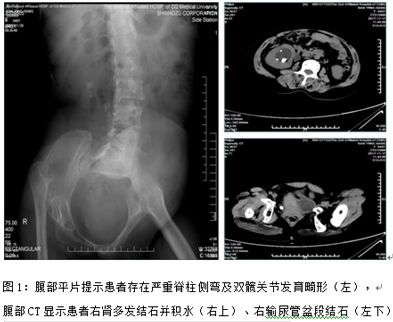

该患者是一位40岁女性,近2月来出现反复发作的右侧腰腹部疼痛,在当地医院行腹部平片提示右肾多发结石、右输尿管多发结石(腹段及盆段结石)。当地医院遂推荐患者于我院就诊。

患者入院后,我科积极完善相关术前常规检查,手术指征明确。同时处理肾及输尿管多发结石已是我科常规手术,不过实施传统输尿管硬镜或软镜手术,需采用截石位摆位,而患者自身条件所限,合并有先天性左髋关节发育不良伴右侧髋关节陈旧性脱位、脊柱严重侧弯畸形,对常规截石位摆位造成了困难。姜庆主任多次组织全科医生讨论,制定了一系列手术方案,我科决定先尝试传统截石位术式,并于2017年11月30日实施手术。术中发现患者双髋关节活动受限,输尿管硬镜仅能窥及右侧输尿管口,多次尝试却无法进入,手术被迫终止。